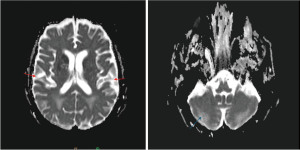

Upon admission, the patient was initially started on intravenous thiamine for possible Wernicke’s encephalopathy and alcohol-withdrawal protocol. Malignancy testing, including CT scan of the chest, abdomen, and pelvis, and testicular ultrasound, were negative. Syphilis antibody testing and CSF and serum panel for autoimmune encephalopathy were negative (Figure 1). Electroencephalogram (EEG) returned negative for any seizure or abnormal electrographic activity. A 5-day methylprednisolone course was attempted to treat an undifferentiated autoinflammatory process without success. A repeat MRI was performed one week later, which revealed diffuse signal abnormality of the right basal ganglia (pulvinar sign) and cortical ribboning, further raising suspicion for CJD (Figure 2). Two days later, approximately ten days into the hospitalization, T-tau resulted abnormal at >20,000 pg/mL (range, 0–1,149 pg/mL), 14-3-3 Gamma resulted at 91,161 AU/mL (range, <30–1,999 AU/mL) and RT-QuIC resulted as positive (reference negative) providing a >98% likelihood of prion disease, so the decision was made to defer brain biopsy. The patient continued to worsen throughout his 3-week hospitalization, and he was transitioned to comfort care with home hospice. He passed away only a few days after discharge, surrounded by his loved ones.

The initial diagnostic modalities include CSF studies, brain MRI, EEG, and CT scan, with the first two being of value. CSF protein 14-3-3 is released into the CSF during cell damage and was the first protein used in diagnosing CJD, although it can be elevated in other disorders with neuronal destruction (11). The sensitivity nears 87% and specificity of 66% which increases to 85% with enzyme-linked immunosorbent assay (ELISA) (11). TAU, another biomarker, is a microtubule-associated protein marking neuroaxonal degeneration. Discrepancy exists on the cutoff value used to differentiate Alzheimer’s dementia from CJD, but a cutoff value of >1,000–1,500 pg/mL, when combined with protein 14-3-3, can increase the sensitivity to 93% and specificity to 98% (11). Newer, more advanced CSF testing, RT-QuIC, detects PRPSC, with a sensitivity of 80–96% and specificity of 98–100% (11,12). MRI brain with and without contrast is another useful study, especially sequences with diffusion-weighted imaging, and fluid-attenuated inversion recovery (FLAIR). Classic abnormalities seen on MRI FLAIR sequence include high signals in the striatum (basal ganglia), cerebral cortex or thalamus (Figure 2) (12). Sensitivity ranges from 92–98%, and specificity is around 93–94% (13). EEG can supplement the diagnosis suggested by 1–2 Hz periodic sharp wave complexes, although this has fallen out of favor with the progression of CSF testing (12). The high specificity of RT-QuIC assay has markedly enhanced the diagnostic utility of cerebrospinal fluid (CSF) analysis in identifying CJD. However, further research is warranted to elucidate the relative performance of brain MRI versus CSF-based assays, as both modalities are currently employed in tandem due to the complex and nuanced nature of CJD diagnosis.